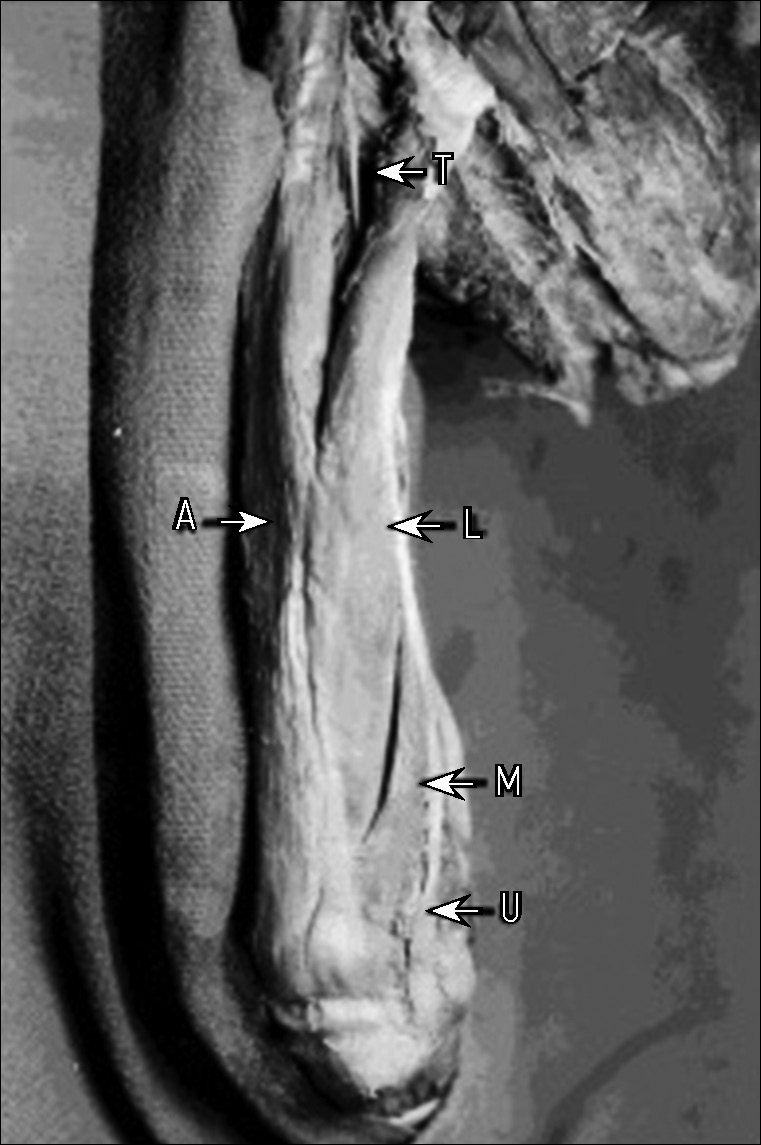

Рис. 2. Изображение задней поверхности дистального отдела левого плеча, демонстрирующее мышечное брюшко четвёртой головки трёхглавой мышцы плеча (М) и сухожилие четвёртой головки (Т) по отношению к мышечному брюшку длинной головки (L), мышечному брюшку латеральной головки (А) и локтевому нерву (U) [4].

Fig. 2. Photograph of the distal aspect of the posterior compart-ment of the left arm demonstrating the muscle belly of the fourth head of the triceps brachii muscle (M) and the tendon of the fourth head (T) in relation to the muscle belly of the long head (L) and the muscle belly of the lateral head (A) and the ulnar nerve (U) [4].